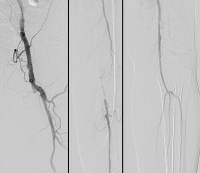

Abbildung 1: Präinterventionelles Angiogramm eines langstreckigen Verschlusses (TASC-C-Läsion) der Arteria femoralis superficialis links.

Keywords:

Angiogramm

,

Gefäßmedizin

TASC-C-Läsion